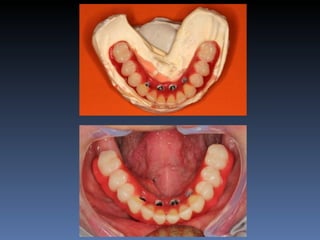

Maria Seemagenn Borges

Diagnóstico: Desdentada

Plano de tratamento: Instalação de 5 implants endo-

ósseos - “Protocolo Branemark”, com carga imediata.